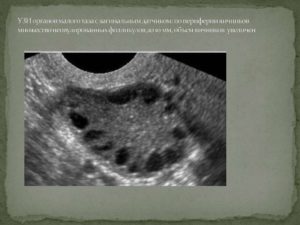

Так выглядят антральные фолликулы на УЗИ

Если фолликулы растут (размеры 10 мм и больше), если процесс затронул и правый, и левый яичник, если сами яичники увеличены, а фолликулов больше 26-30, то диагностируют развитие поликистоза.

Заболевание не соответствует своему названию, так как на яичнике киста не образуется. Болезнь характеризуется наличием большого количества элементов, расположенных по всей периферии яичников.

Такое количество фолликулов не позволяет созреть «лидеру», тем самым мешая овуляции, а следовательно, и беременности.